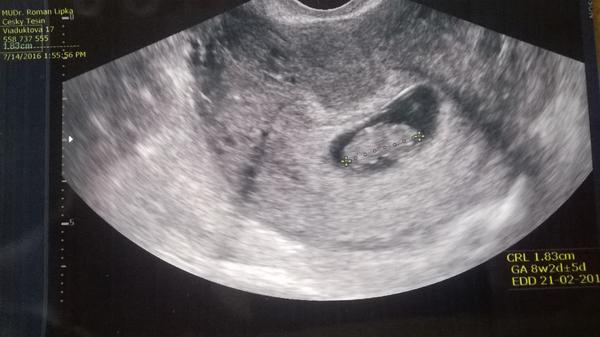

ahojky, tak já byla na UTZ minulé pondělí, dle MS jsem byla v 5.tt, doktor teda říkal,že to vypadá na 4.tt a je to taky taková malá tečka, foto přikládám: